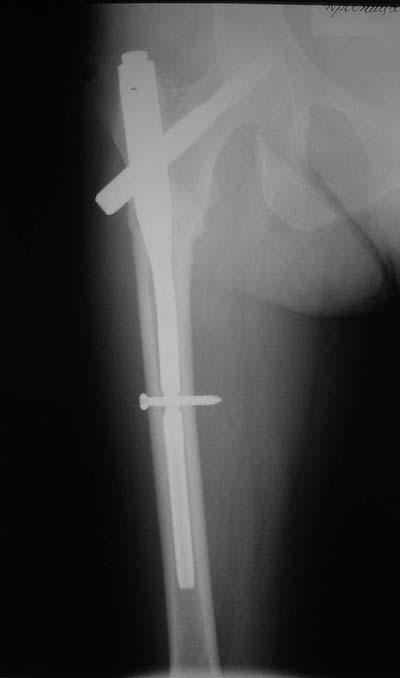

> Я имею ввиду довольно редкий простой поперечный перелом на 1-2 см

> ниже малого вертела.

Тут шеечный винт не фиксировал бы периферический отломок, так что конечно, дистальный винт был бы нужен. Хотя для такого перелома вообще короткий штифт какой-то неуютный выбор.

Не думаю так. см вложение.

> Не думаю так. см вложение.

Для такого перелома вполне может быть использован диафизарный штифт, который отечественного производства я даже боюсь считать во сколько раз дешевле... Недавно несколько примеров я закидывал.